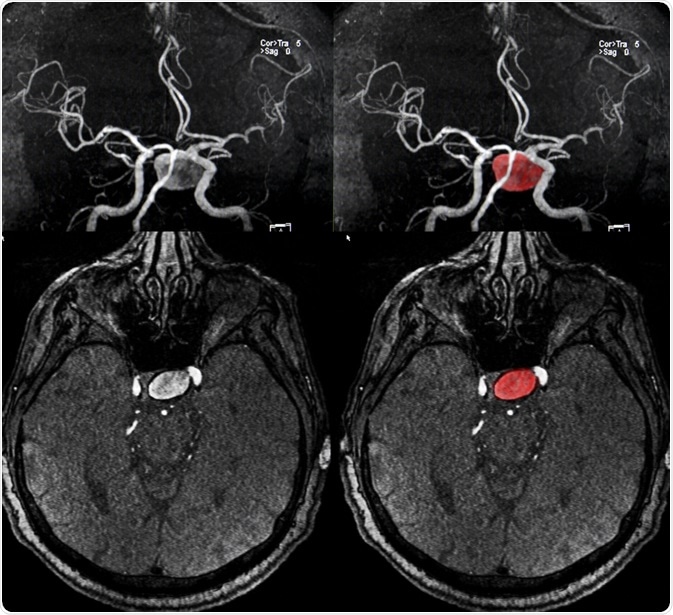

A brain (cerebral) aneurysm is a weak spot in an artery in the brain that swells and fills with blood.

The bulging area within a cerebral aneurysm can put pressure on surrounding tissue or a nerve. The aneurysm can also rupture, spilling blood into the brain tissue. This is referred to as a subarachnoid hemorrhage.

In most cases, a cerebral aneurysm does not cause any symptoms and goes unnoticed; however, in rare cases, the aneurysm ruptures, causing a hemorrhage and stroke. Depending on how severe the hemorrhage is, a person may suffer brain damage or even die. Cerebral aneurysms can occur anywhere in the brain, but the most common location is a loop of arteries found at the base of the brain, referred to as the circle of Willis.